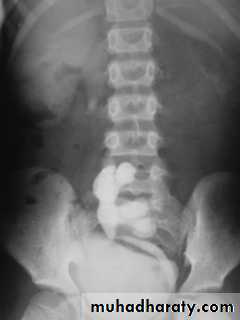

Ectopic kidney:

- Result from halted ascend of kidneys during fetal development

- Often are incidental findings during routine ultrasound, -usually located in the lower abdomen and rotated, -short ureter.

-Chronic pyelonephritis, calculi and hydronephrosis are more common .